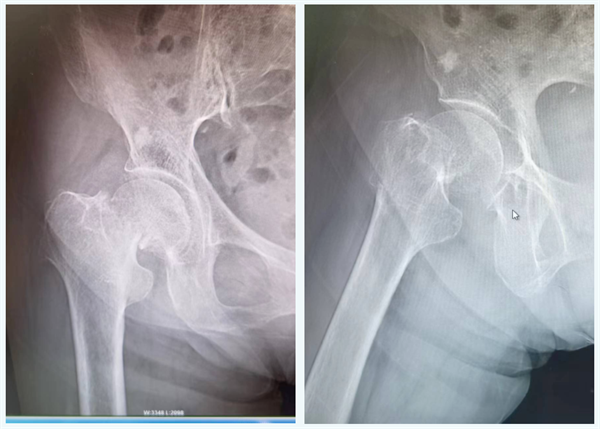

患者程xx(化名),102岁,因在家坐板凳时不小心摔伤致右髋部肿痛、畸形、功能障碍1天。于我院就诊,门诊行DR片示右侧股骨颈骨折,遂入院行手术治疗。

术前影像: